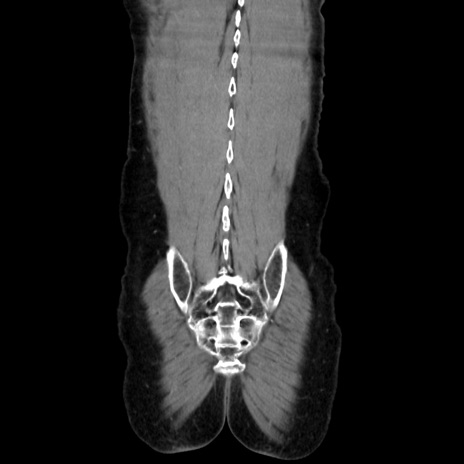

横断像